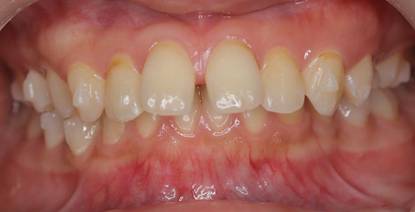

インビザラインによる矯正症例2 22歳女性

治療開始時。正中離開と過蓋咬合がありました

治療途中 5か月後

治療終了 治療開始後7か月